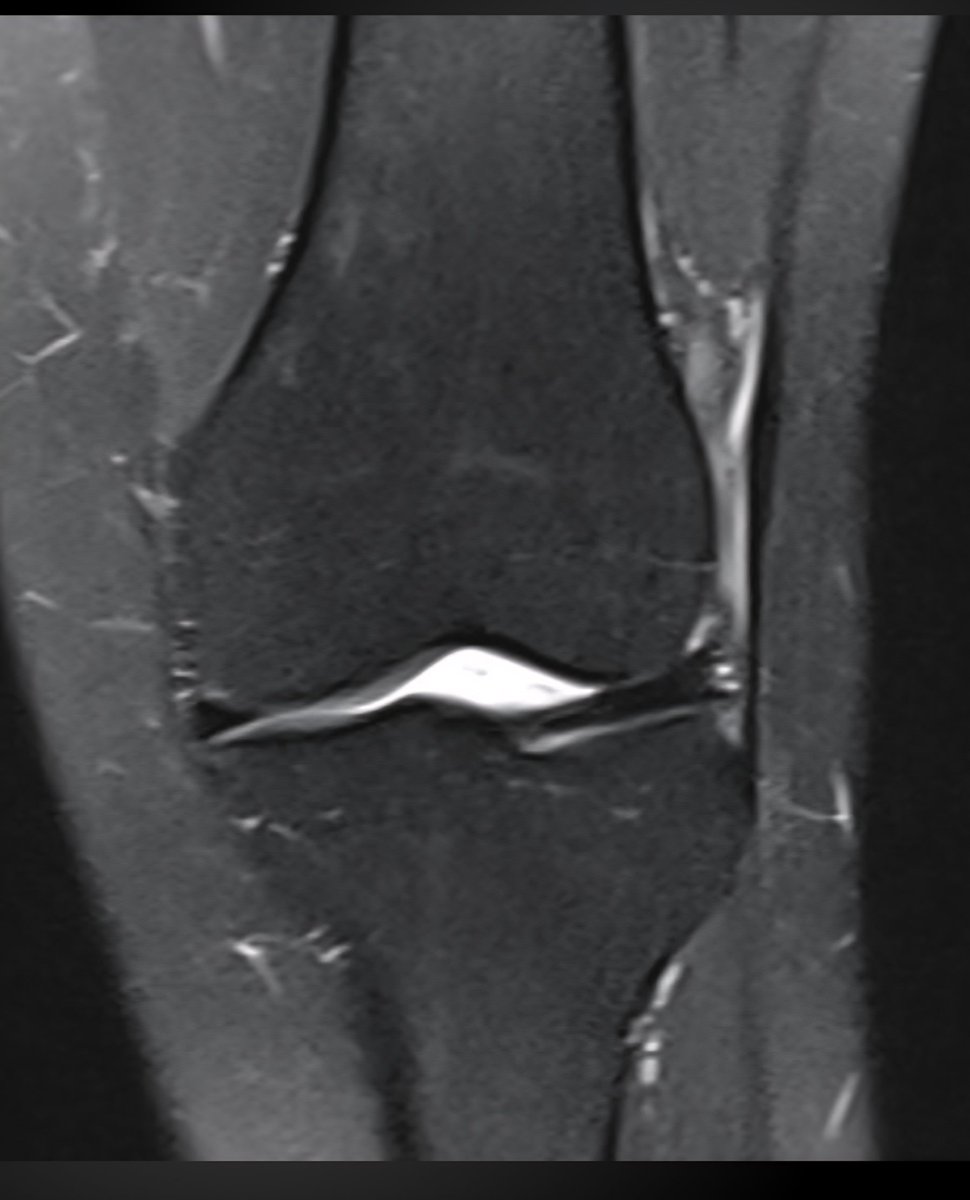

Consent ✅ Right hip pain & stiffness Both hip joints show OA changes - but R more advanced than L Why?